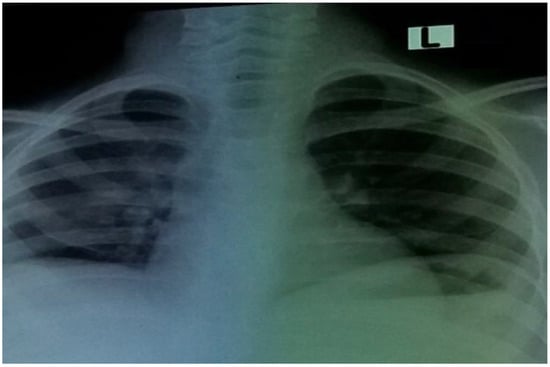

On day seven following admission, the patient’s overall health improved, and the chest X-ray showed effusion improvement (Figure 4).

Figure 4. Chest X-ray of patient showing resolution of right pleural effusion on hospital admission day 7.